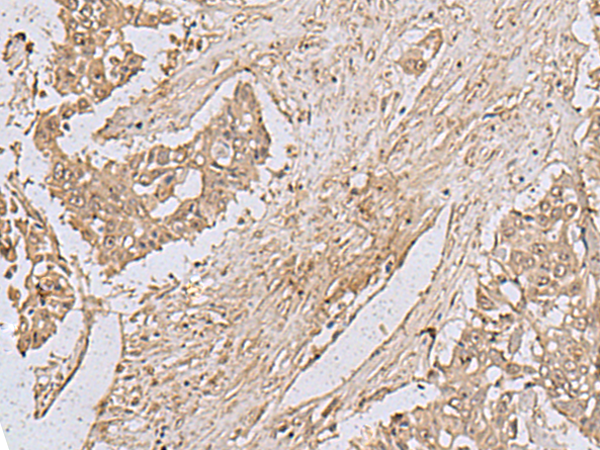

IHC positive control:

Human liver cancer and Human colorectal cancer

IHC Recommend dilution:

50-100